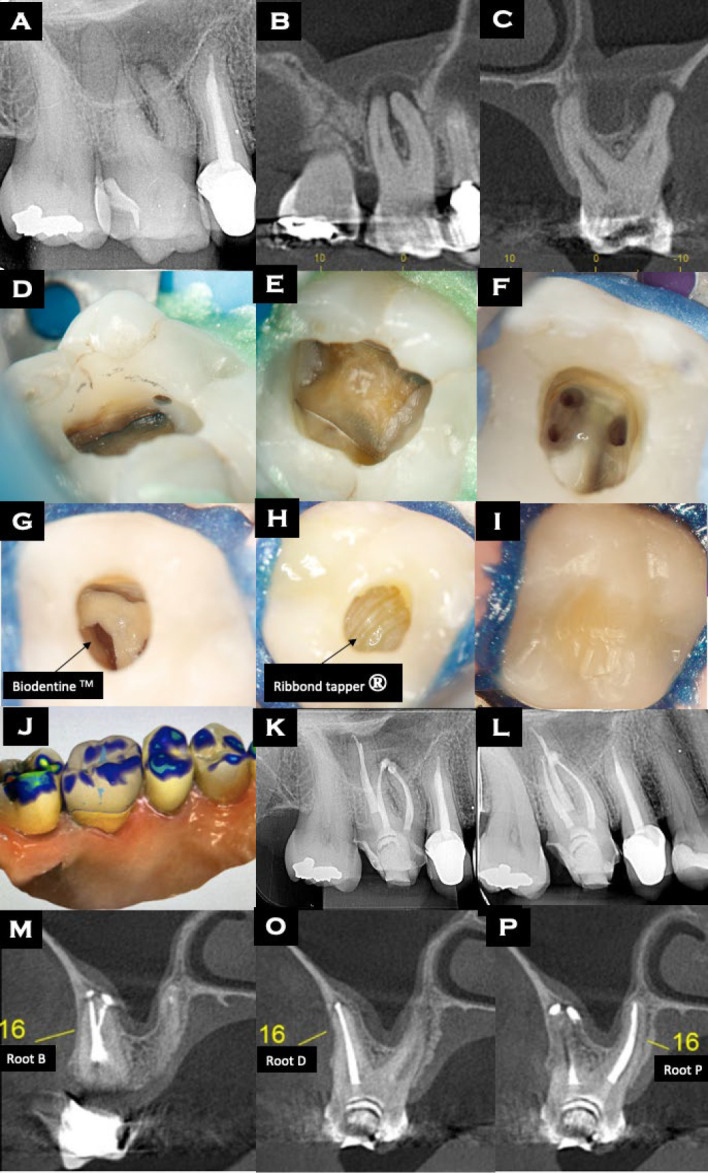

Restoring endodontically treated teeth (ETT) that exhibit cracks, enlarged roots, or weakened root walls is a frequent challenge in dental practice. The present study describes three cases in which contemporary restorative techniques were employed and suggests that applying Ribbond tape (RT) to ETT can improve fracture resistance and better prevent the propagation of cracks compared with traditional methods. Although extensive in vitro research has been conducted on fiber-reinforced composites, studies evaluating the clinical use and durability of fiber-reinforced composites to restore ETT are limited. This report strictly adhered to the case report (CARE) guidelines, and the treatments were initiated only after signed informed consents were obtained from the patients. Therefore, the old restorations were removed from the teeth that required intervention and composite resin core build-up was created, followed by endodontic treatments or retreatment. Subsequently, the endodontic accesses were reinforced with RT. The protective restorations were performed and bonded. The two-year follow-ups showed that the patients had complete remission of signs and symptoms, and they remain under monitoring. The study emphasizes the importance of internal reinforcement of ETT and strengthening weakened walls with a resin core build-up reinforced with fibers like RT. This approach enhances mechanical retention, inhibit fracture propagation, and establish a strong chemical bond between RT and resin. It is suggested to be a promising strategy for increasing the longevity and strength of the teeth, providing a conservative and effective alternative to traditional methods.